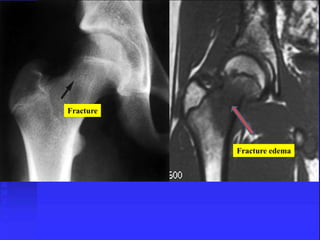

Stress fracture

Callus due to Fracture

Fracture

Fracture edema